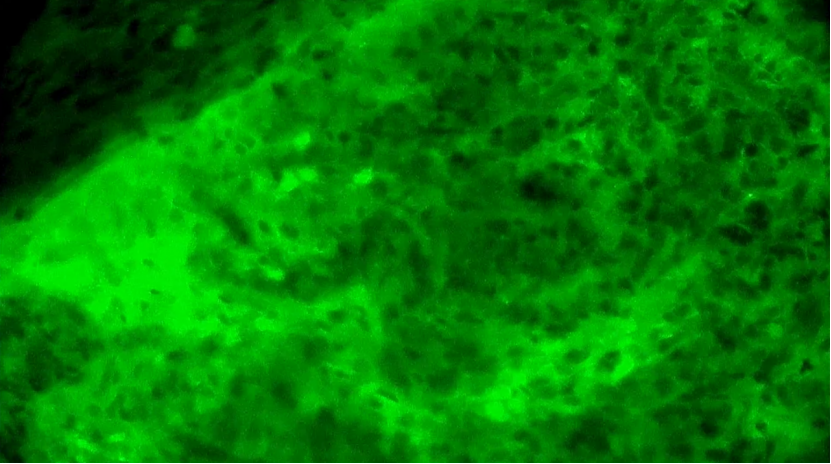

術(shù)中EndoSCell?細(xì)胞圖像如下:

第1次掃查離體腫瘤組織,細(xì)胞核異型性明顯,分布不規(guī)則且密度高,陽性。

第2次掃查瘤腔,一處組織的細(xì)胞核異型性明顯,分布不規(guī)則,密度較高,陽性。